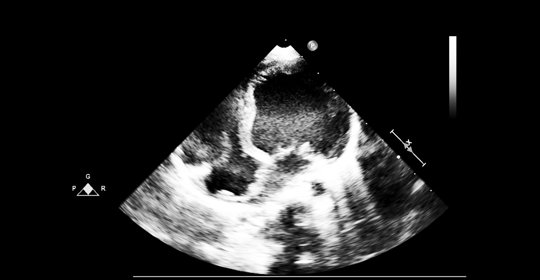

建議定期進行超音波心動圖監測以評估二尖瓣狀況,同時注意避免劇烈運動,保持良好的生活習慣,保證充足的休息時間。